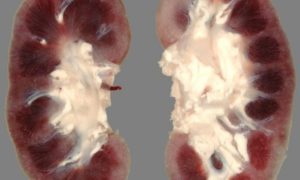

Вовремя не диагностированный и нелеченый гломерулонефрит переходит в хроническую форму и приводит к почечной недостаточности. Почки сморщиваются, уменьшаясь в размерах, и не могут полноценно выполнять свою функцию.

При прогрессирующеем течении, неотвечающий на активную иммунодепрессивную терапию, хронический диффузный гломерулонефрит переходит в свою конечную стадию — вторично-сморщенную почку.

Важно давать себе отчёт о том, что любое проявление хронического гломерулонефрита может перейти в острую форму этого заболевания, а клиническая картина будет практически такой же, как при остром гломерулонефрите. Вне зависимости от формы этого заболевания, со временем оно становится причиной развития вторично-сморщенной почки, что ведёт к появлению хронической почечной недостаточности.